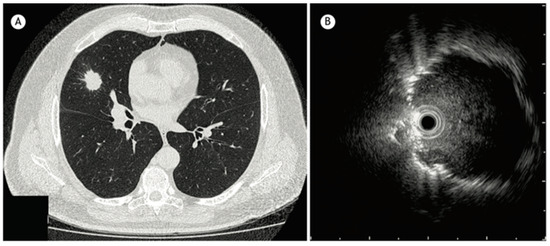

Radial endobronchial ultrasound (R-EBUS) is a diagnostic tool used in pulmonary medicine to visualize and evaluate lung lesions, particularly those not visualized by standard bronchoscopy. It involves the use of a rotating ultrasound probe (20-Mega Hertz) that is flexible and feeds through the working channel of a bronchoscope that emits ultrasound waves at 360 degrees to create detailed images of the lung tissue and surrounding structures (Figure 2). The probe is advanced into the tracheobronchial tree to reach the target lesion. The diagnostic yield of a transbronchial biopsy using a radial probe along with bronchoscopy is approximately 66.7% [13].

Figure 2. (A) CT chest showing a 2.5 cm nodule in the middle lobe. (B) Radial EBUS image reproduced from Jacomelli et al., 2015 [13] (Shared under the terms of the Creative Commons Attribution License, https://creativecommons.org/licenses/by/4.0/).